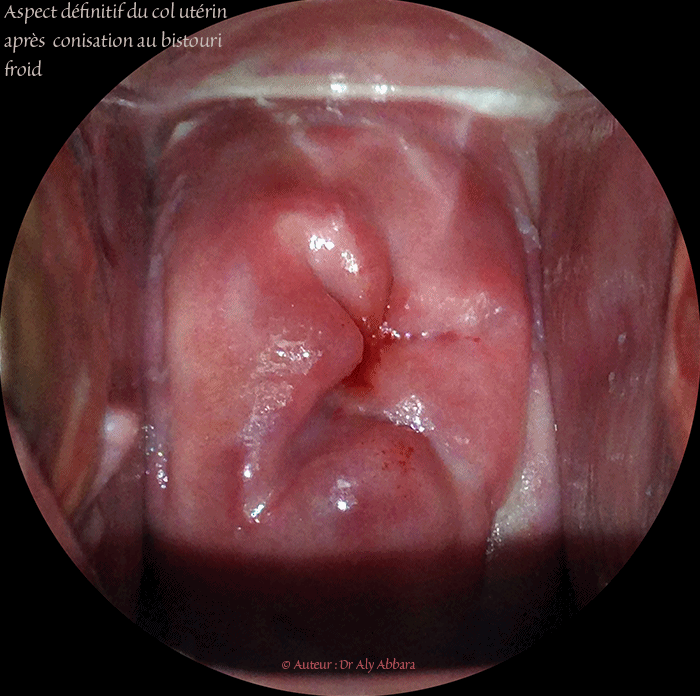

| Image clinique montrant l'aspect définitif du col utérin après une conisation (biopsie coniforme) réalisée cinq ans auparavant chez une femme multipare, ayant dans ses antécédents deux accouchements normaux par voie naturelle. Il s'agit d'une conisation effectuée par la technique utilisant le bistouri froid ; l'indication de l'acte opératoire fut la présence d'une lésion cervicale de haut grade (CIN II). On observe comme conséquence de cette conisation l'irrégularité cicatricielle de l'orifice externe du col utérin (comparé à l'orifice externe d'un col utérin d'une femme multipare ou nullipare sans antécédents de conisation). مظهر عنق الرحم عند إمرأة ولود أُجريت لها منذ خمس سنوات عملية اِستئصال أذية داخل البشرة العنقية من الدرجة الثانية (CIN II) بعملية الخزعة المخروطية بالمشرط البارد. النتيجة الواضحة الوحيدة لهذه العملية الجراحية هو عدم إنتظام الفوهة الخارجية للقناة العنقية الرحمية. |